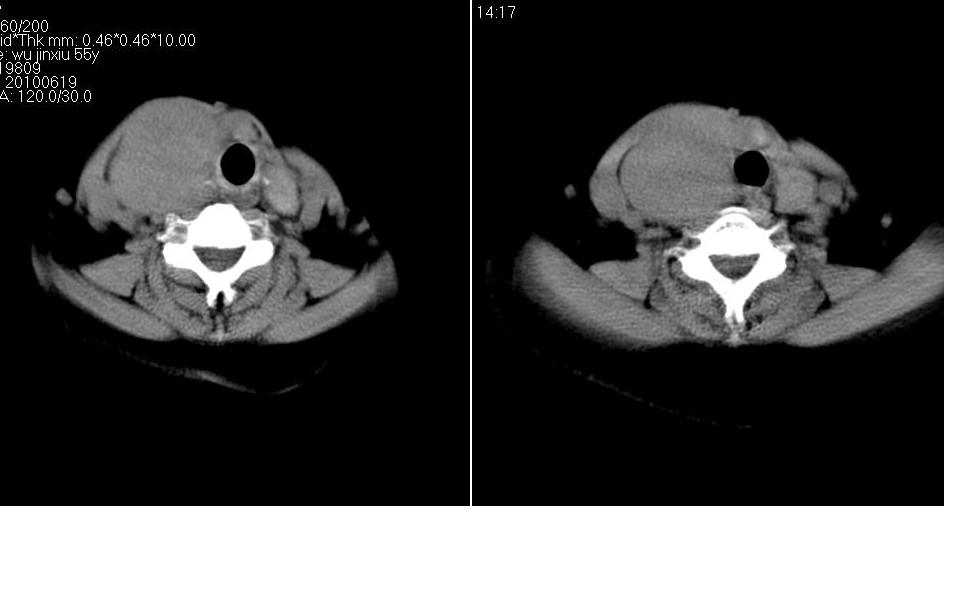

标题: CT27207:颈部CT平扫

女 55岁 右侧颈部包块十年余,自己感觉有增大。

来源于右侧甲状腺  边界清晰,内可见点状钙化,向下生长达前上纵隔血管间隙内  考虑甲状腺腺瘤并胸内甲状腺肿